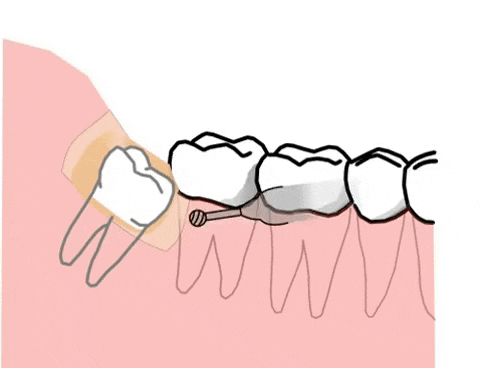

1.位置不正,常见于下颚智齿

智齿向前生长挤压到邻牙。此外,向后、向舌侧、向颊侧、甚至向下长也都可能产生危害。

智齿生长方向不正常,通常会导致智齿与相邻的磨牙间出现缝隙或凹槽,极易嵌顿食物残渣,长时间清理不净,相邻磨牙将发生龋齿、牙髓炎、根尖炎等。